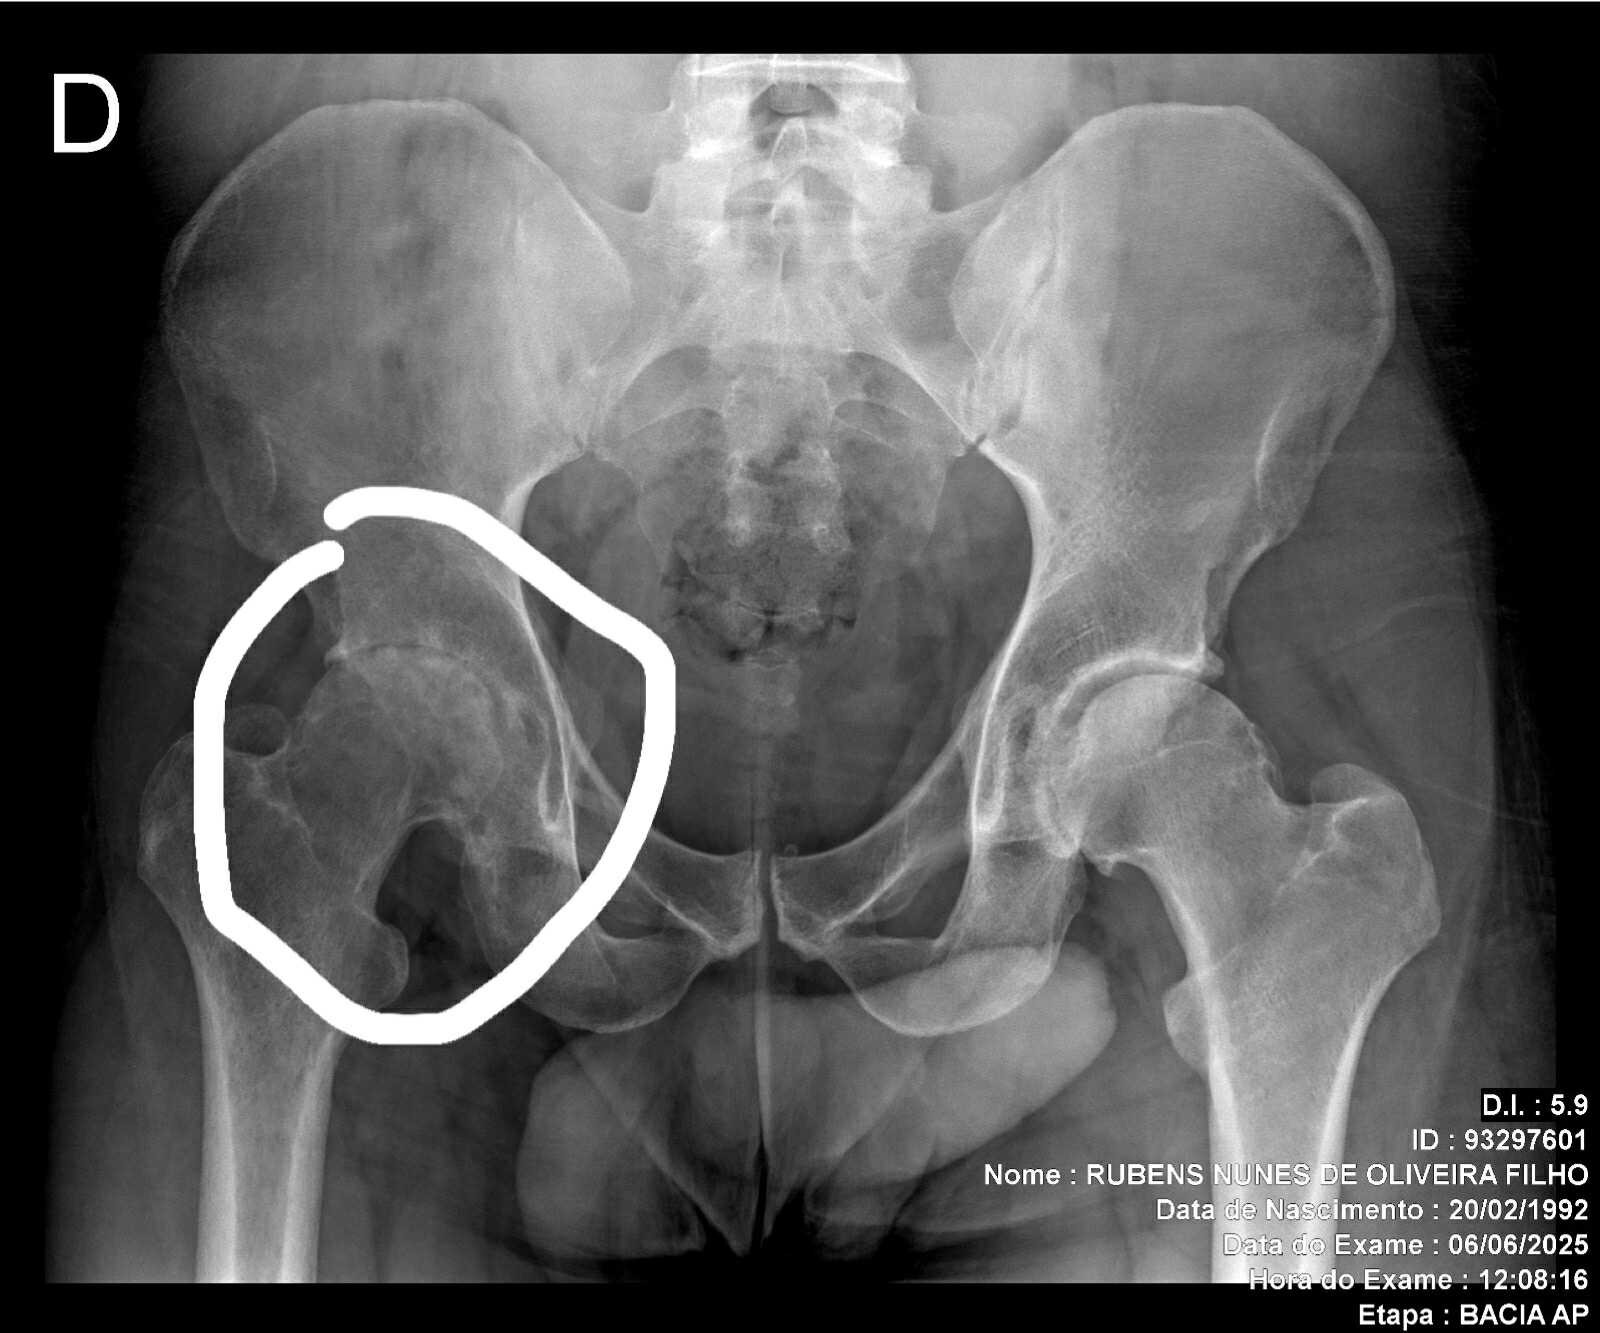

Rubens and I have known each other several years now. He was working in the US and during that time he became an integral part of Stealth Brazilian Jiu-Jitsu. Rubens was training with us on a Monday and Tuesday was in and out of hospitals.

A severe infection took hold, relentlessly traveling down the spine and settling in the hip. This resulted in a protracted hospital stay of 37 days, causing significant disruption and discomfort. US Medical interventions proved insufficient in addressing the persistent infection. The complexities of the case demanded specialized attention and a comprehensive treatment plan.

Rubens flew to Brazil to get the life saving medical care that US doctors weren't giving him.

Despite the efforts made, the infection remained a challenge, impacting overall health and well-being. The extended hospitalization underscored the severity of the situation.

Professor Rubens is going to need another surgery to repair his hip fully. There is a doctor in his home country of Brazil that can perform the surgery but since he was in the USA his government benefits take 2 years to get reinstated in Brazil.